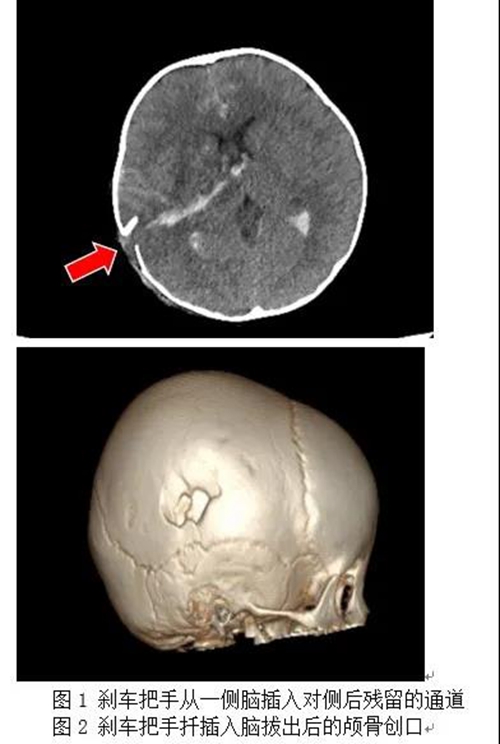

当时,2岁的糖糖在外面玩耍时不慎碰倒了路旁的电动车,电动车刹车把手插入孩子的颅内。惊慌失措的糖糖家人赶紧将电动车从孩子身上搬走,并拨打“120”急救电话求救。

满头是血的糖糖被“120”紧急转入青岛妇女儿童医院儿童急诊意外伤害门诊。因穿通伤导致大脑严重受伤,糖糖一直处于抽搐昏迷状态,儿童创伤科医生马上为患儿进行病情评估和镇静止惊治疗,在控制患儿惊厥持续状态后医护人员立刻通过“儿童严重创伤绿色通道”将其转入儿童重症监护室(PICU)。

经麻醉科、检验科、输血科多方积极准备,糖糖到院后1个小时就顺利进入手术室,手术开始!术中,儿童创伤科(神经外科)孙勇主任主刀,第一时间为糖糖清除嵌入脑组织内粉碎的颅骨残片、快速控制因脑部血管撕裂导致的出血并清除坏死脑组织。由于患儿是异物脑穿透伤,术后脑组织极有可能出现继发严重脑水肿,孙勇主任凭借多年的危重颅脑损伤抢救经验,决定去除右侧大面积骨瓣以帮助糖糖度过术后的颅高压危险期,同时放置脑室内颅内压监测装置,以便术后进行重症神经监护管理,为患儿争取更好的预后。